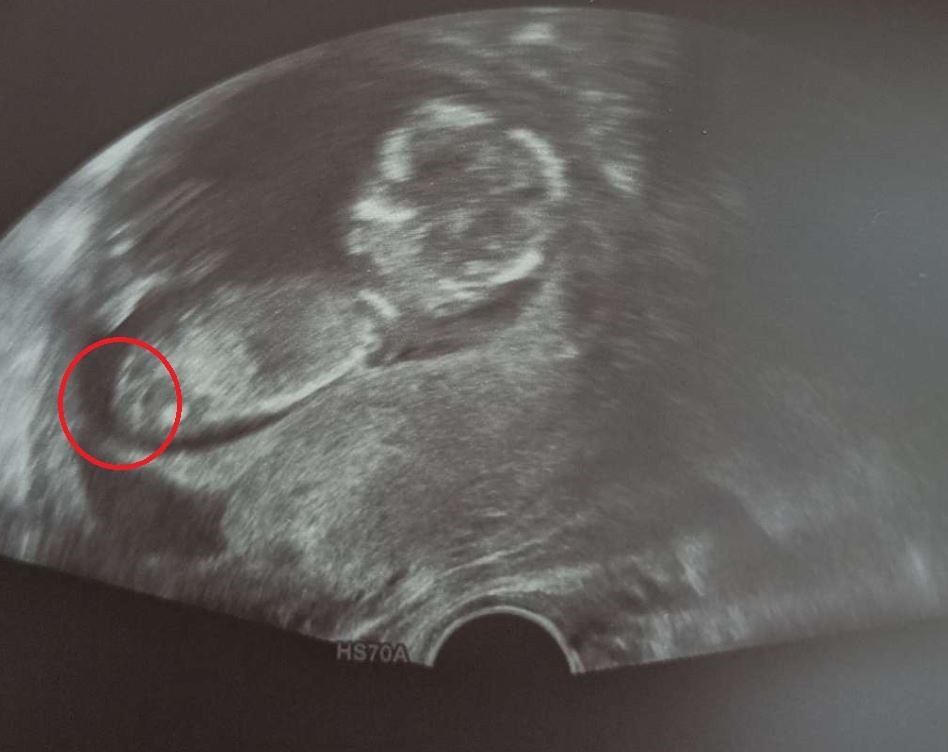

Hej kobietki widać coś waszym zdaniem?

Ja widzę ślicznego dzidziusia😍

A tak na serio to poczekaj do połówkowych. Ja wiem, że chcesz wiedzieć, ale przy tych pierwszych USG o pomyłkę nie trudno.

Lepiej poczekać i mieć pewność, niż się nastawić a potem zawieść.

Poza tym czemu po prostu nie spytałaś lekarza? Wtedy lekarz może spróbować lepiej ustawić zdjęcie. Nie mówiąc już o tym, że 2023 roku bez problemu mamy dostęp do badań nipt i już po 10 tygodniu ciąży w kilka dni ma sę 99,9% pewności co do płci dziecka